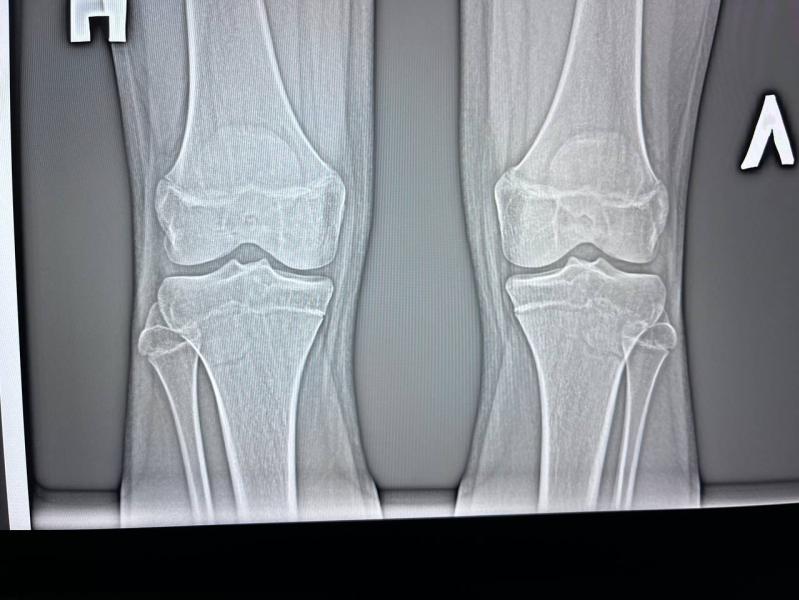

Артрит у подростка 14 лет: что видно на рентгене в 2-х проекциях?

post image 3

Неделю назад поставили артрит в 2-х проекциях, сегодня сделали рентген, кто-то разбирается ? Здесь что-то видно ?

Подросток 14 лет…